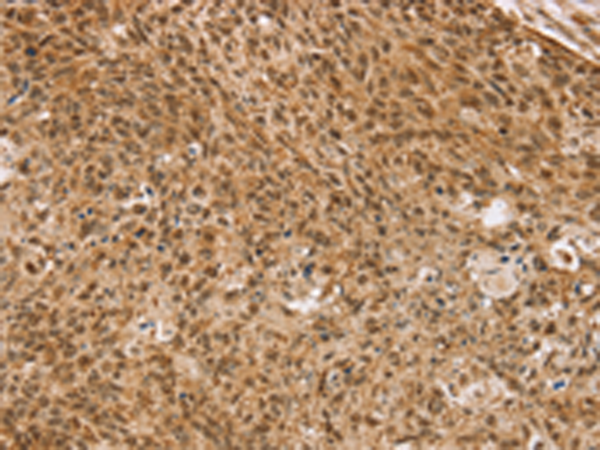

分类: 科研抗体货号: P08826别名:应用: IHC反应种属: Human, Mouse, Rat